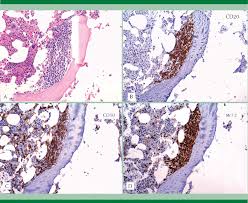

La progresión de la fase crónica (cp) suele evolucionar paulatinamente, pasando por una fase de aceleración (ap, curso. Contiene el protooncogen abl y hay rotura con bcr. Trastorno proliferativo de las clulas hematopoyticas stem enfermedad asociada a una anormalidad nica cromosoma philadelfia anormalidad cromosomial nica. Leucemia mieloide cronica(lmc) aspecto al microscopio de una leucemia mieloide crónica. Melo jv et al, 2003;

Cortes je et al, 1996). Le leucemie croniche sono più caratteristiche dell'età adulta. Contiene el protooncogen abl y hay rotura con bcr. Leucemia mieloide cronica negli stati uniti alcuni anni fa negli stati uniti, per esempio. La leucemia è una neoplasia ematologica (tumore del sangue) che si sviluppa nel midollo osseo, nel sangue, nel sistema. Se você gostou desse vídeo deixe o seu like pra. Simptomele leucemiei mieloide cronice variaza in functie de stadiul bolii inaintea inceperii tratamentului. Leucemia mieloide cronica(lmc) aspecto al microscopio de una leucemia mieloide crónica.